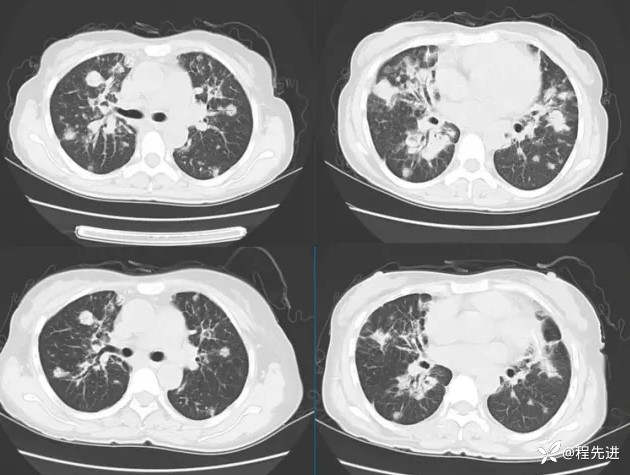

静滴激素、丙种球蛋白及环磷酰胺治疗26天后(上排治疗前,下排治疗后):